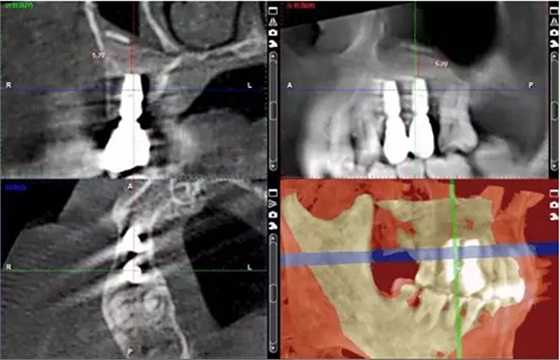

術(shù)后14個月